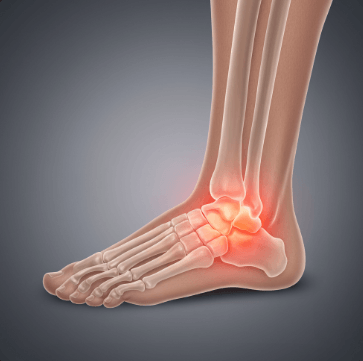

복숭아뼈는 발목 안쪽과 바깥쪽에 튀어나온 뼈로, 정식 명칭은 '복사뼈'입니다.

이 부위에 통증이 생기는 가장 흔한 원인은 발목 염좌예요. 발을 헛디뎌 인대가 늘어나거나 찢어지면서 복숭아뼈 주변에 통증과 부기가 생깁니다.

▫️ 체중을 전혀 실을 수 없을 정도로 심한 통증

▫️ 발목이 심하게 붓고 멍이 광범위하게 생긴 경우

▫️ 발목 모양이 변형되거나 불안정한 느낌